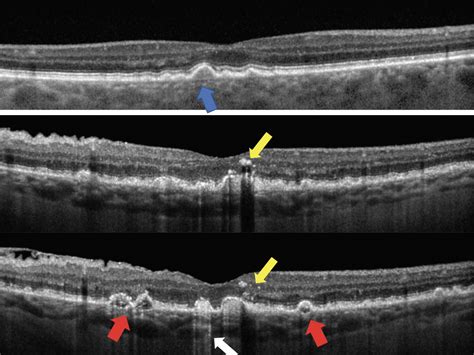

2. Optical Coherence Tomography (OCT): This is a non-invasive imaging scan that provides a high-resolution, cross-sectional view of the retinal layers. It is the gold standard for tracking changes in drusen over time.